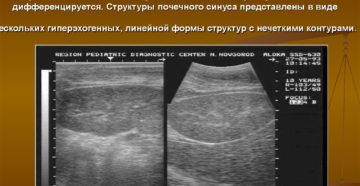

Повышена эхогенность почек плода Внутриутробное развитие всегда вызывает много переживаний. Но современные методы диагностики способны…